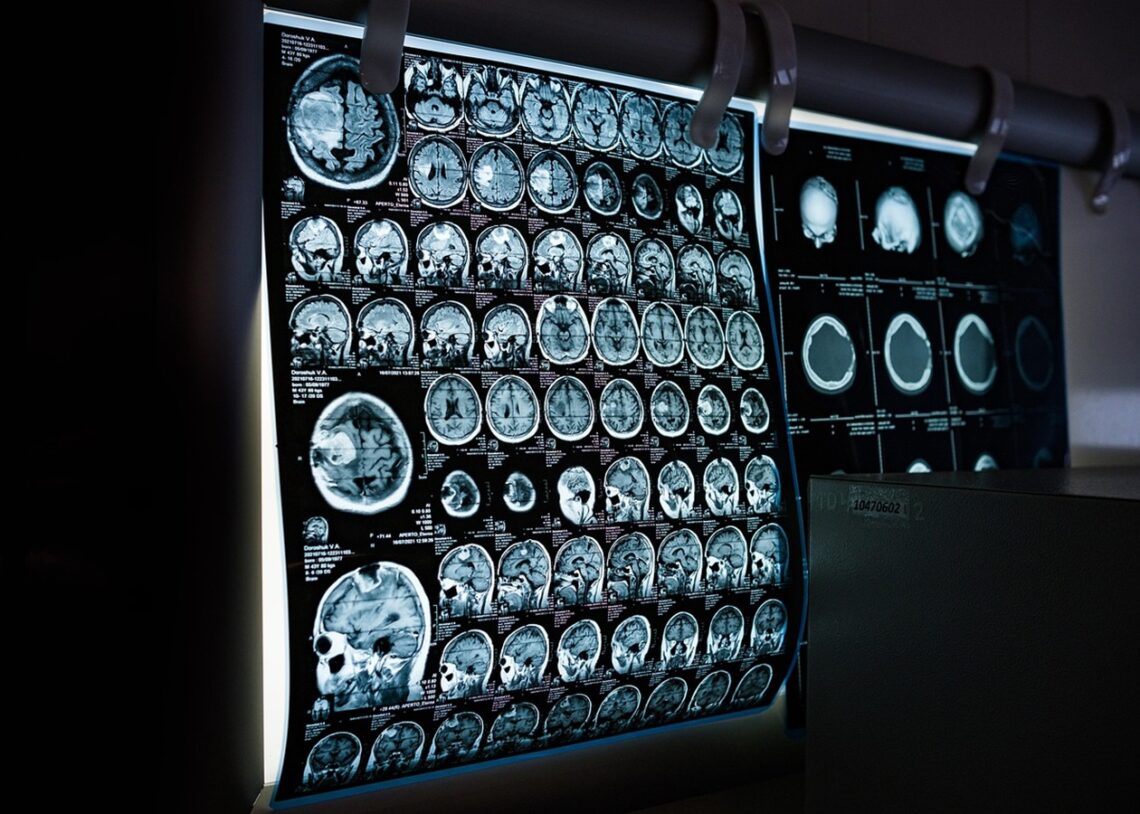

Зміни у зовнішності, включно з набряками губ, збільшенням пальців і ширшим обличчям, тривалий час списували на стрес. Після переїзду до Нью-Йорка стан погіршувався, і лише у приватній клініці в Колорадо після МРТ та аналізів встановили правильний діагноз: рівень гормону росту у Седорік був утричі вищим за норму, а на гіпофізі виявили 1,4-сантиметрову макроаденому.